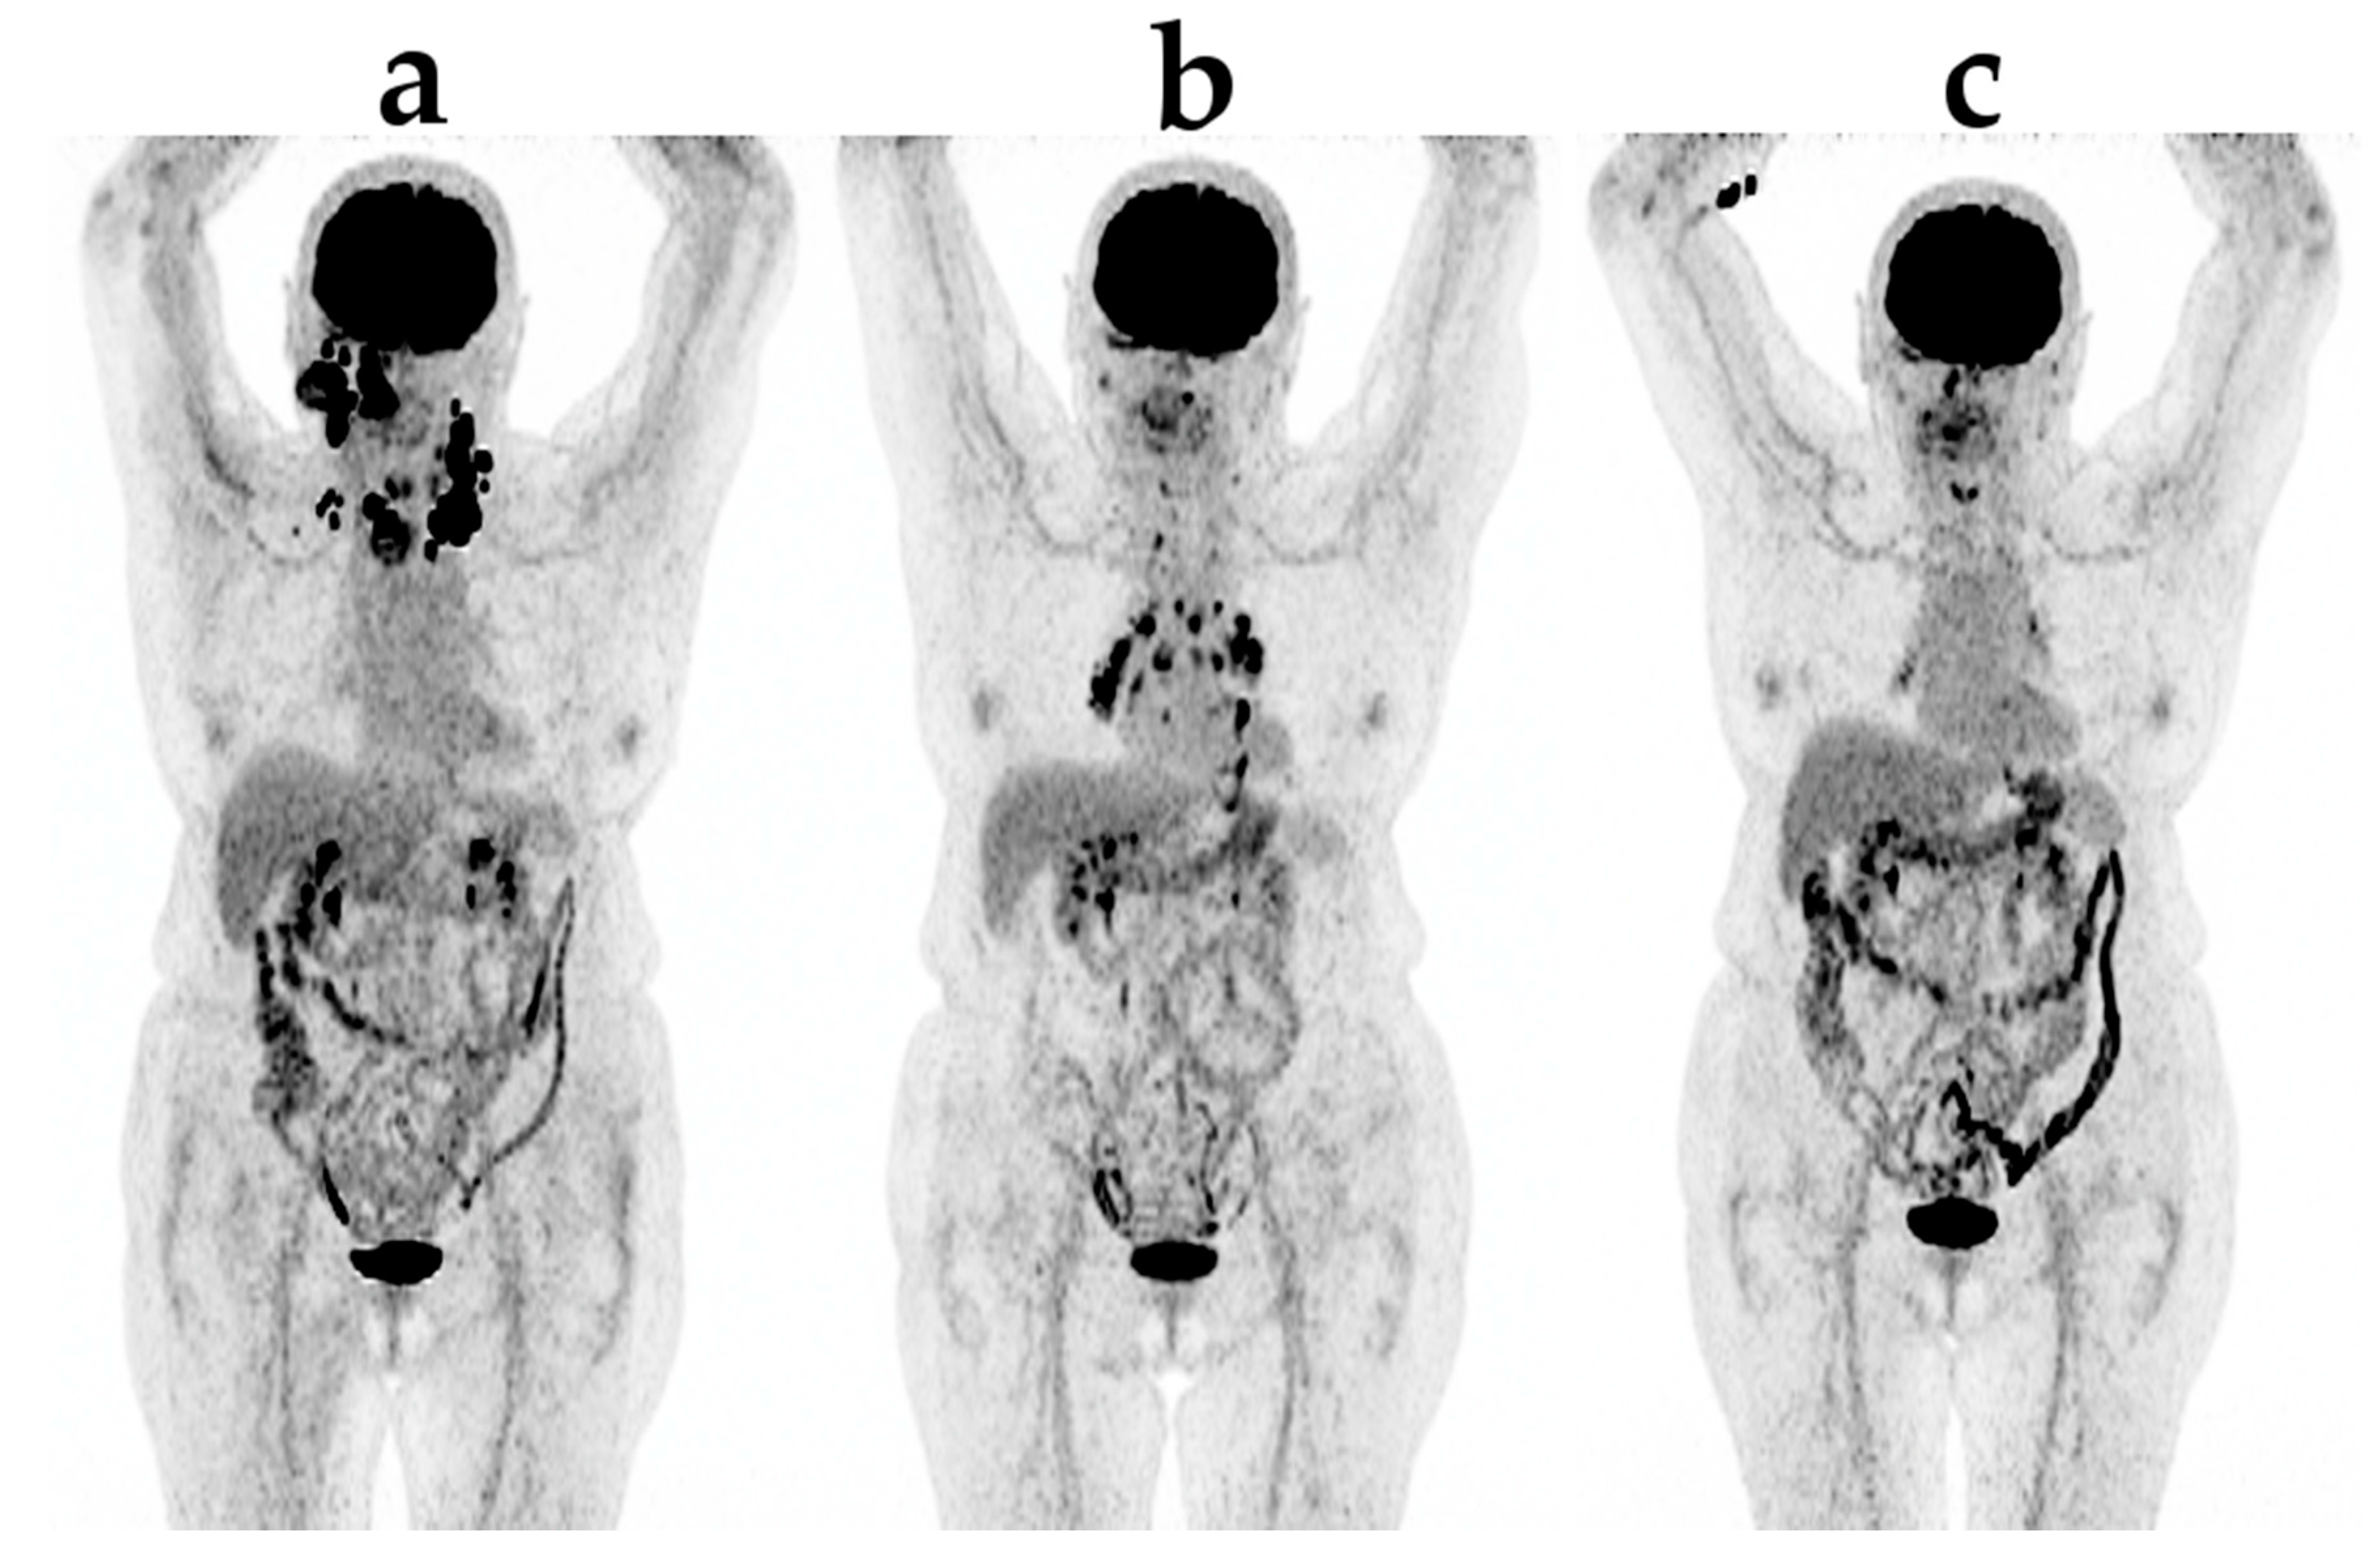

Figure 2. An example of new lesions appearing in an otherwise responding patient due to sarcoid-like irAE (immunerelated adverse event): (a) before treatment; (b) after three series of pembrolizumab; (c) after six series of pembrolizumab.

Using metabolic response evaluation with FDG PET, no formal criteria exists for ICT. Increased tumor burden, it being in FDG-uptake (SUV) or a number of FDG-avid lesions, is usually classified as progression according to the PERCIST and EORTC criteria, both developed for evaluation during chemotherapy [39]. However, care must be taken when new lesions appear in an otherwise responding patient as this could also be due to irAE (Figure 2), e.g., when seen in the adrenals, bowel or pituitary [40].